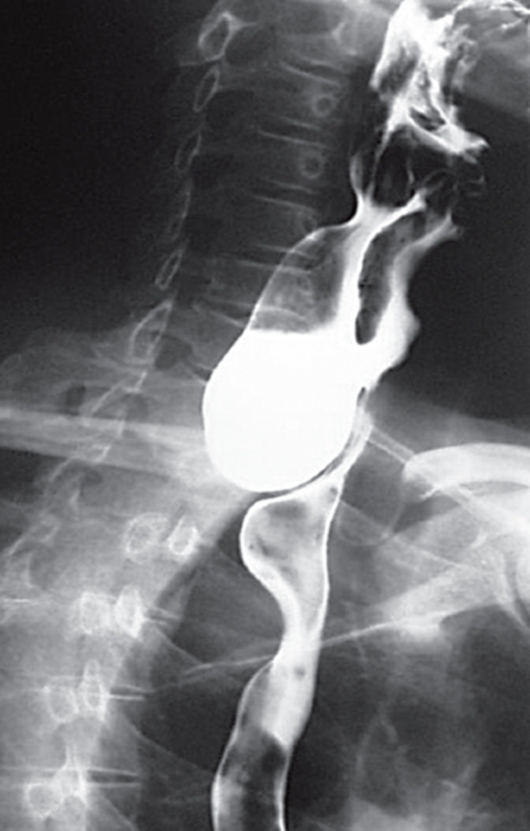

Больного, 60 лет, беспокоят боли за грудиной и по ходу позвоночника, отрыжка воздухом и пищей с неприятным запахом. Умеренная отрыжка воздухом существует давно. Иногда во время приема пищи отмечал тяжесть за грудиной и в межлопаточном пространстве. В последнее время стали постоянными отрыжка воздухом и пищей с неприятным запахом, ощущение инородного тела за грудиной, периодически в течение нескольких часов наблюдаются нарушения глотания и прохождения пищи по пищеводу. После искусственно вызванной рвоты эти явления проходят. В рвотных массах - пища с дурным запахом (рис. 26).

Рис. 26